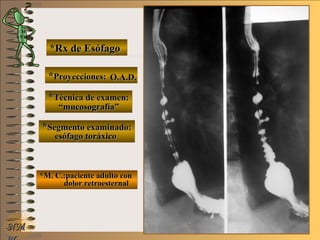

*Rx de Esófago*Rx de Esófago

**Proyecciones:Proyecciones:

**Técnica de examen:Técnica de examen:

**Segmento examinado:Segmento examinado:

*M. C.:paciente adulto con*M. C.:paciente adulto con

dolor retroesternaldolor retroesternal

O.A.D.O.A.D.

““mucosografía”mucosografía”

esófago toráxicoesófago toráxico

A-A-El examen es normal o patológico?El examen es normal o patológico?

Examen patológico de esófago toráxico con téc-Examen patológico de esófago toráxico con téc-

nica de mucosografía y en proyecciones O.A.D.nica de mucosografía y en proyecciones O.A.D.

B-B-La patología es congénita o adquirida?La patología es congénita o adquirida?

Patología adquiridaPatología adquirida

C-C- Dicha patología es orgánica, funcional o mixta?Dicha patología es orgánica, funcional o mixta?

Patología adquirida funcionalPatología adquirida funcional

D-D-Puede describir la o las imágenes patológicas?Puede describir la o las imágenes patológicas?

Se identifican ondas terciarias, no propulsivas queSe identifican ondas terciarias, no propulsivas que

enlentecen el traslado del bolo baritado; tambiénenlentecen el traslado del bolo baritado; también

se distingue una imagen diverticular en borde an-se distingue una imagen diverticular en borde an-

terior de tercio medio de esófago toráxicoterior de tercio medio de esófago toráxico